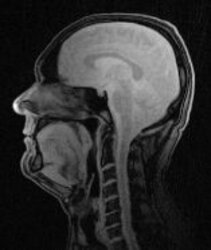

Vocal Tract ImagingThe aim of this project is to acquire images of the vocal tract of performing singers inside the MRI. There are still many open research questions in singing, concerning register changes, the number of registers and general acoustic resonance properties of the vocal tract.

We have ongoing projects to measure singers with real-time sequences in high field MR systems. Additionally we do research on position-related changes of the vocal tract with weight-bearing imaging.

The main challenge in this area of research is to accelerate the imaging process. The acquisition can be improved by using non-cartesian trajectories, such as radial or spiral sampling. The acquired data is then processed by using regularized iterative reconstruction methods.